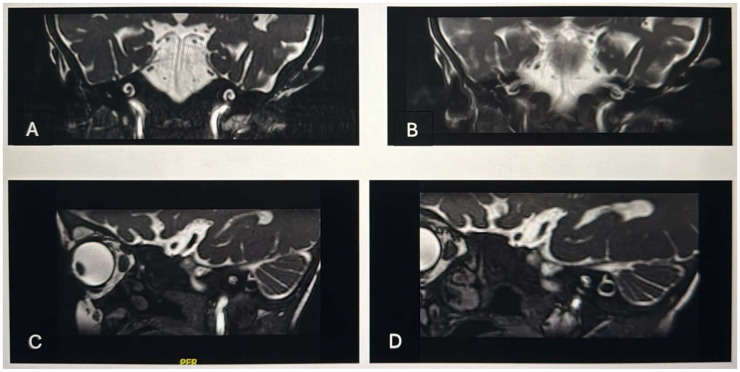

巴特综合征(Bartter syndrome, BS)是一种常染色体隐性遗传病,其特征为羊水过多、早产、多尿、肾盐消耗、低钾血症代谢性碱中毒、肾素和醛固酮水平升高、血压正常以及听力下降。BSND、CLCNKA和CLCNKB的突变导致了这种疾病。我们报告了一名3岁的女孩,患有BS 4型和感音神经性听力损失,在听力筛查失败后接受了人工耳蜗植入(CI)。患者成功地进行了左侧皮瓣植入,但后来发生了皮瓣感染,最初用抗生素治疗,并使用带血管的皮瓣进行手术修复,但失败了。在同样的修复过程中,右耳被成功植入。第三次手术需要移除左侧植入物并用颞顶叶瓣缝合伤口,这是通过整形手术完成的。这是在BS中最早的关于管理设备挤压的报告。文献综述强调,在每个综合征组中,BS患者CI的结果存在显著差异,并且额外残疾的存在加剧了这种多样性。我们的病例说明CI可以改善BS患者的生活质量,但多学科团队对于管理这些病例至关重要。我们强调需要进一步的研究来评估现实的结果和并发症发生率,因为这将指导未来的治疗策略。

Bartter syndrome (BS) is an autosomal recessive disorder characterized by polyhydramnios, premature birth, polyuria, renal salt-wasting, hypokalemic metabolic alkalosis, normal blood pressure with increased levels of renin and aldosterone, and the presence of hearing loss. Mutations in BSND, CLCNKA, and CLCNKB cause the disorder. We present a 3-year-old girl with BS type 4 and sensorineural hearing loss who received cochlear implantation (CI) after failing a hearing screening. The patient had a successful left-side implantation but later developed a flap infection, initially treated with antibiotics and surgical repair using a vascularized flap, which failed. During the same repair procedure, the right ear was implanted successfully. A third surgery was required to remove the left implant and close the wound with a temporoparietal flap, performed by plastic surgery. This is the earliest report on managing device extrusion in BS. The literature review highlights that the outcomes of CI in patients with BS vary significantly within each syndrome group and that the presence of additional disabilities accentuates this diversity. Our case illustrates that CI can improve the quality of life for patients with BS, but a multidisciplinary team is crucial for managing these cases. We stress the need for further studies to evaluate realistic outcomes and complication rates, as this will guide future treatment strategies.